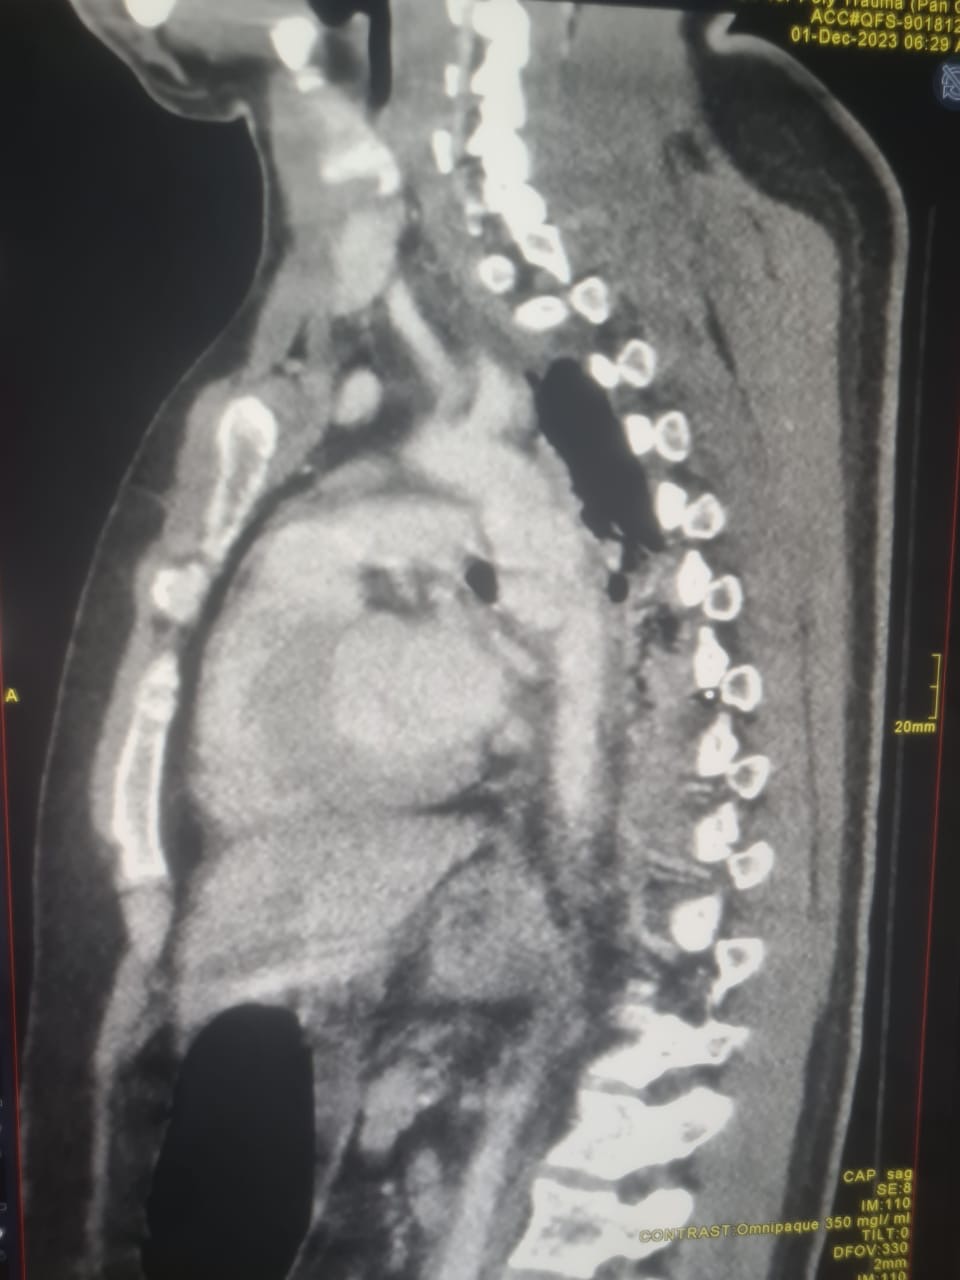

وفي التفاصيل أوضح التجمع أن المريض راجع المستشفى كان يعاني من تسلخ بالشريان الأبهر الصدري بسبب حادث مروري، واظهرت الفحوصات الطبية التي أجريت له وجود تمزق بالطبقة الداخلية للشريان تسببت بفصل الطبقات الداخلية والوسطى لجدار الشريان والتي في بعض الحالات قد تتسبب بالوفاة لا سمح الله.

وأكد أنه بعد معاينة الحالة من قبل الجهاز الطبي في وحدة الأوعية الدموية إجراء تدخل مباشر عبر القسطرة التداخلية وتركيب دعامة بالشريان الأبهر (الأورطي) الصدري والتي تعرف باسم” TEVAR ” حيث تم تركيب الدعامة بواسطة جهاز القسطرة الجديد المخصص لمثل تلك العمليات، وبعد نجاح العملية غادر المريض المستشفى بالسلامة بعد يومين من العملية وهو بصحة وعافية ولله الحمد.